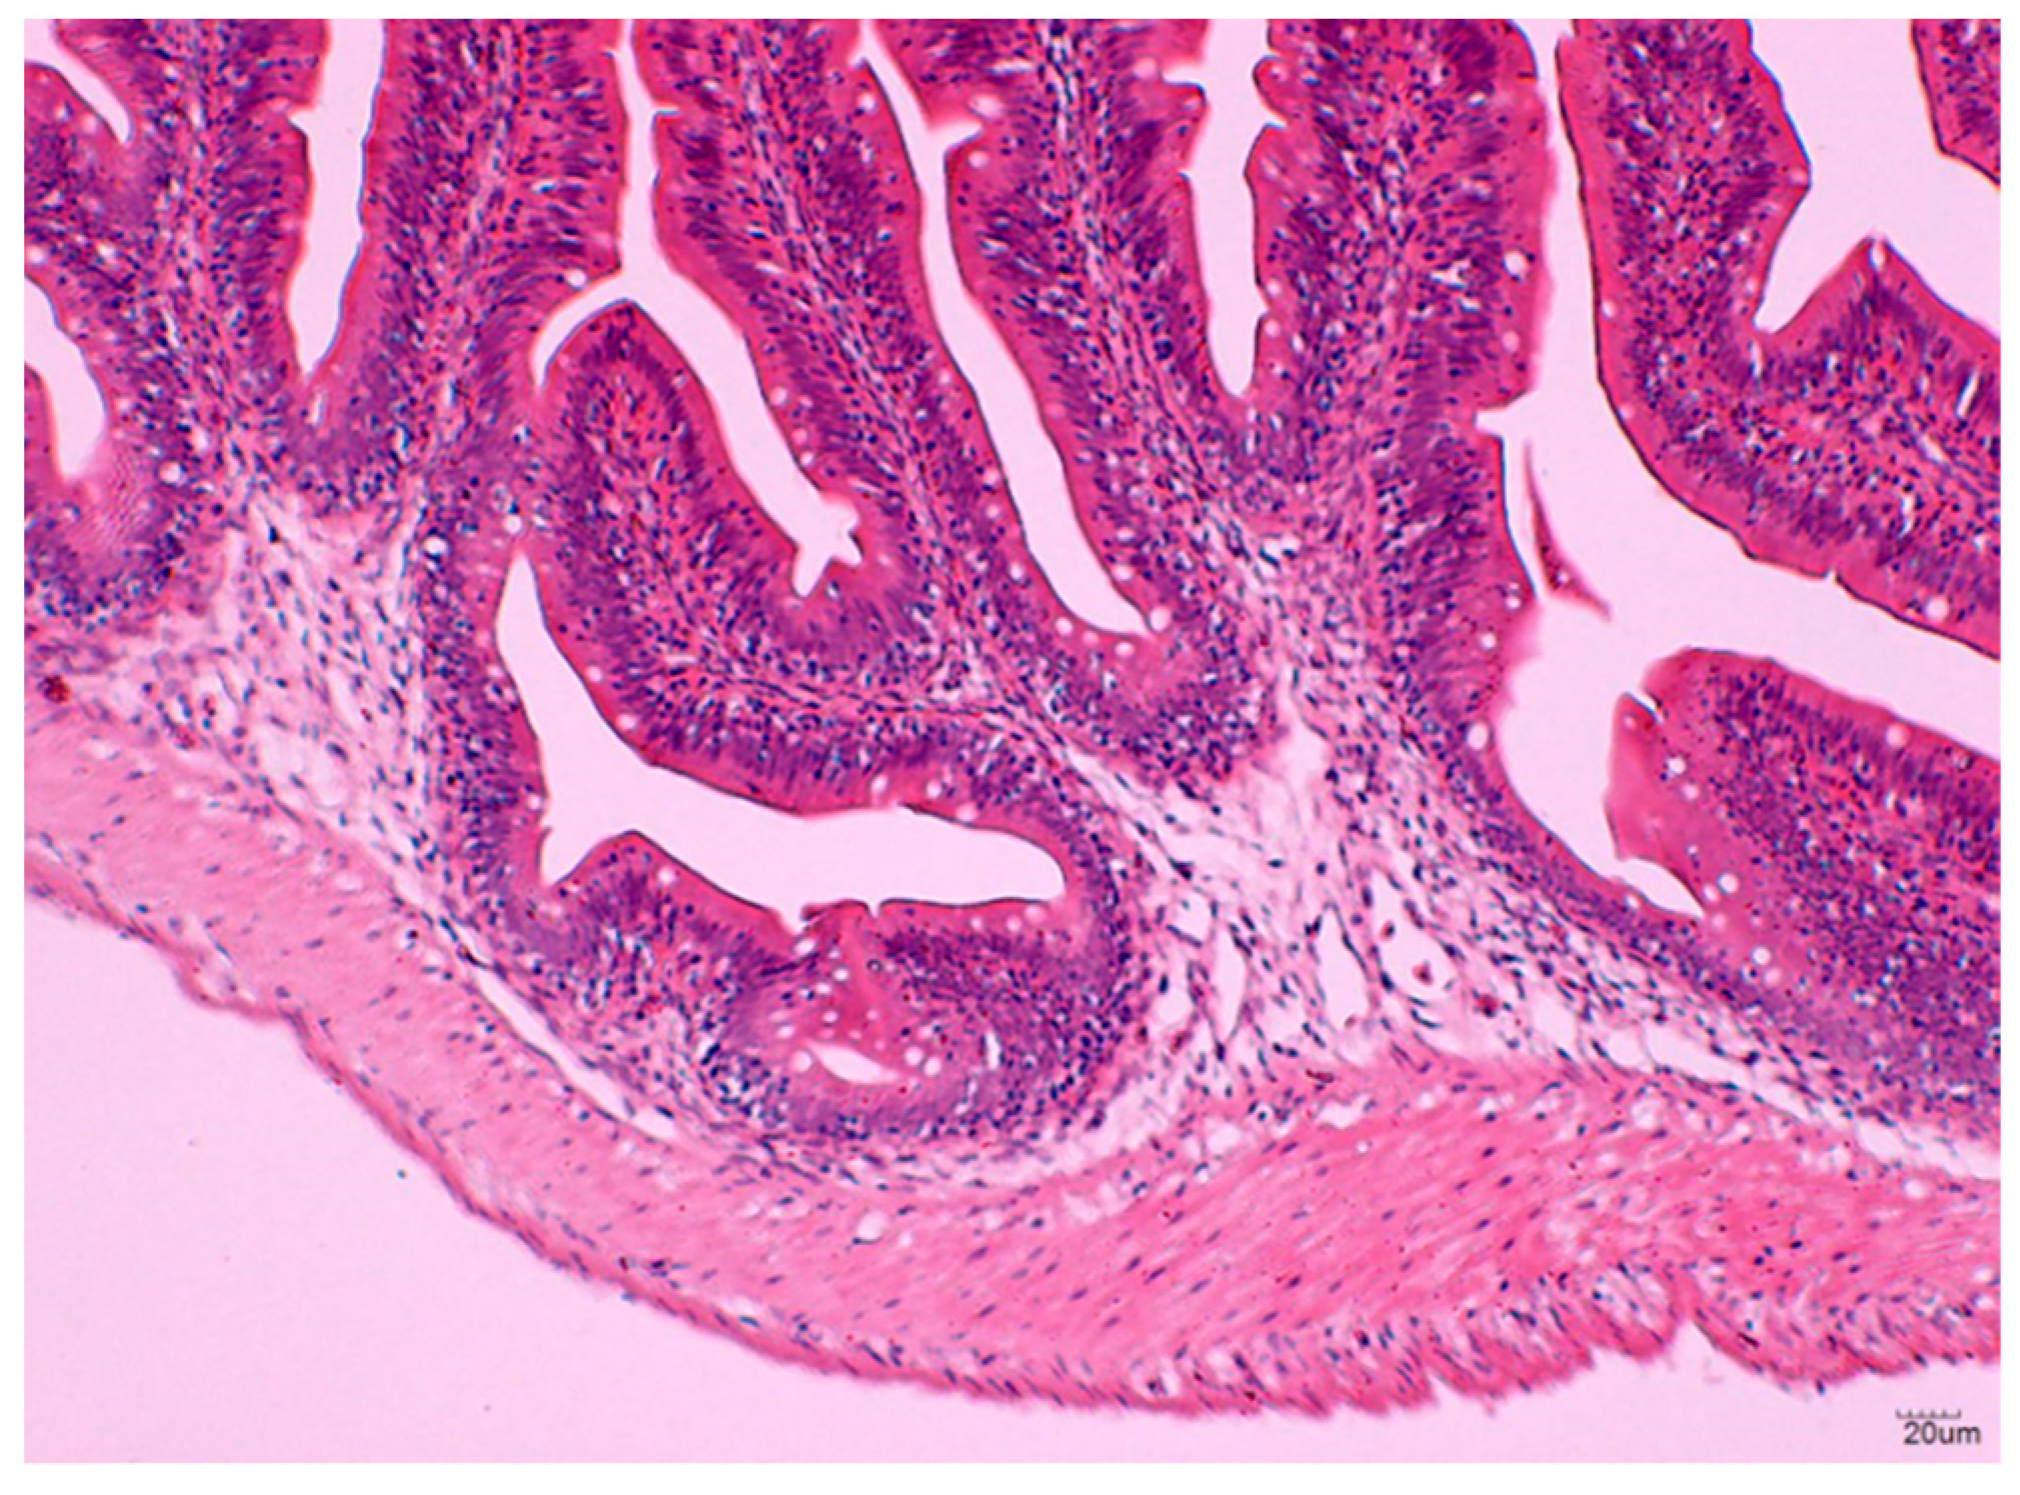

3.2.3. Histological Analysis of the Hindgut

3.2.4. Size of the GALT in Different Vaccination Groups

3.2.5. Number of Lymphoid Cells